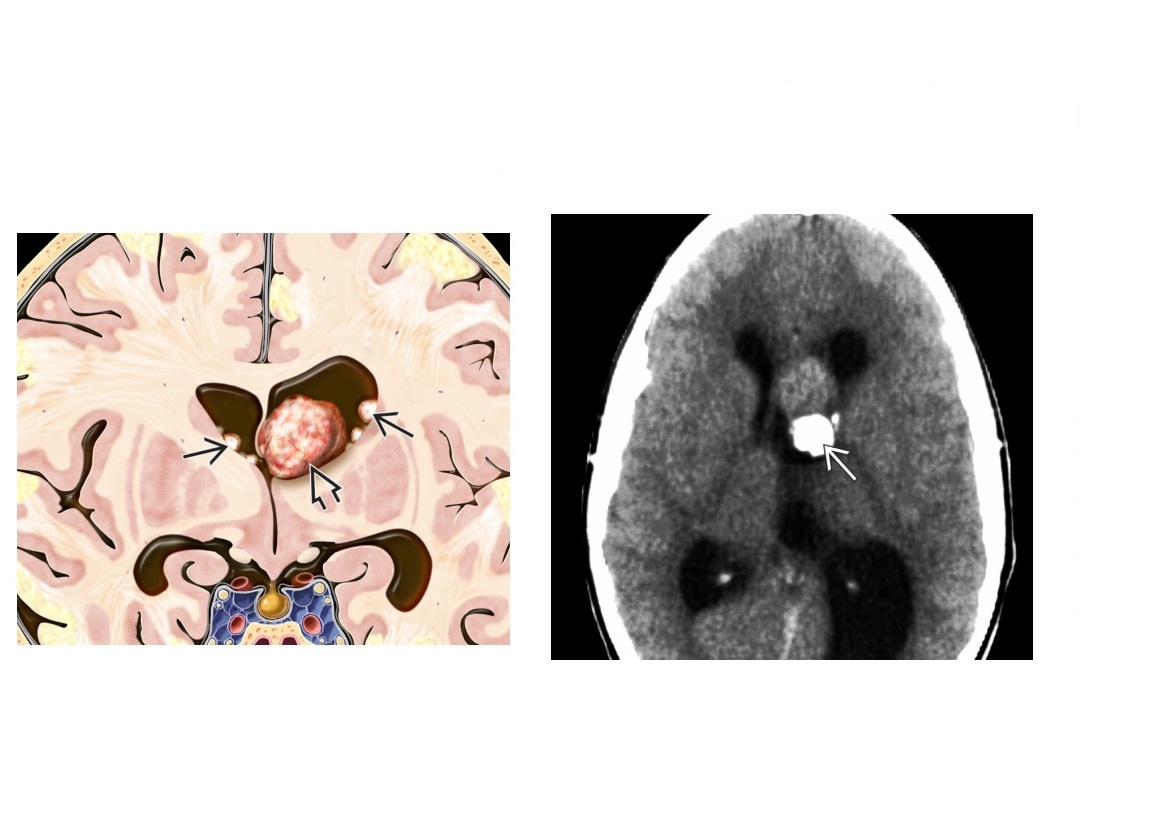

Pineal mass in boy with precocious puberty?

Germinoma **Pineal mass with Central localized Ca⁺⁺ & bithalamic extension** Nb Germinoma and Pineoblastoma difficult to differentiate on imaging. *Can be Suprasellar mass with diabetes insipidus (DI)*

29

Child with large, heterogeneous hyperdense pineal mass with peripheral Ca⁺⁺

Pineoblastoma **Scattered ("exploded") Ca⁺⁺ rather **than localized ("engulfed") Ca⁺⁺ in germinoma